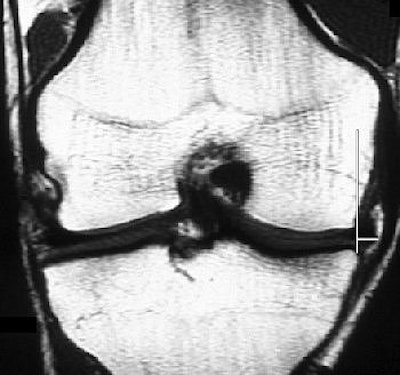

![]() |

| T1-weighted coronal image of right knee at midpoint in 20-year-old asymptomatic male athlete shows medial meniscal extrusion of 5.7 mm. Meniscal extrusion is measured by distance from perpendicular line to edge of tibial plateau and edge of meniscus (white lines). Vertical tear of medial meniscus and sclerosis of subarticular medial tibial plateau with small marginal osteophyte indicating degenerative change are present. No joint effusion is shown. Rennie WJ, Finlay DBL, "Meniscal Extrusion in Young Athletes: Associated Knee Joint Abnormalities" (AJR 2006; 186:791-794). |